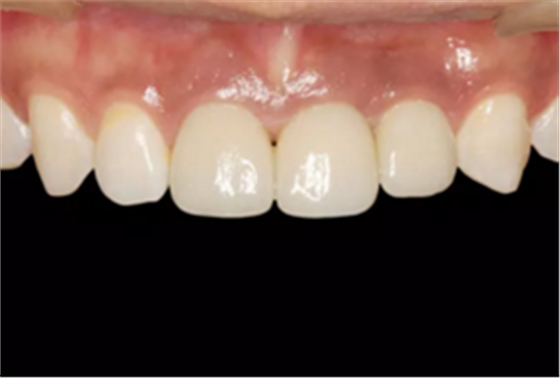

图1 术前微笑像

图2 术前口内像

图23 最终修复后即刻口内像

图25 最终修复后复查口内像